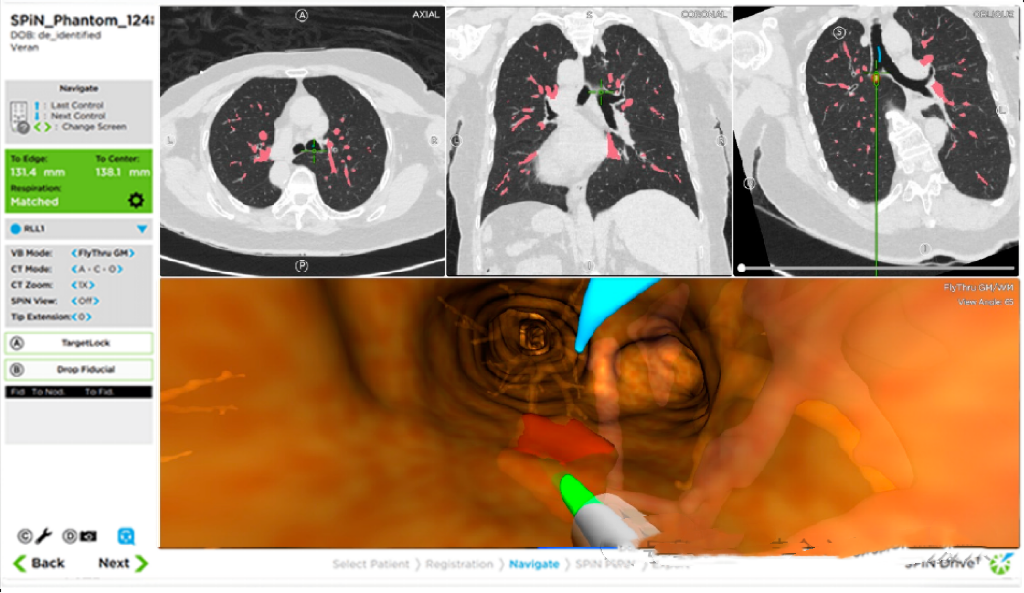

ENB和VBN作为导航支气管镜的主要技术之一,近年来在PPLs的临床诊断中得到了广泛应用,ENB代表产品有Veran SPiN™、superDimension™等,VBN代表产品有Archimedes™、LungPro™、Bf-NAVI™、DirectPath™等。

■ Veran ENB程序

术前CT扫描:在ENB手术当天,对患者进行了双相(吸气和呼气)1mm层厚的CT扫描检查,用于创建更接近生理肺体积的术前虚拟图。

在CT扫描前,需要在患者前胸放置导航跟踪垫(vPad2患者追踪器,INS-0050),可以在整个过程中实现自动注册、指导导航和跟踪患者呼吸状态。

术前计划:在确定目标病变后,创建通往肺病变的规划路线。

术中导航:患者被置于仰卧位并进行全身麻醉,在开始导航前,Vern 有一个可移动式磁场发生器和导航跟踪垫,可实现自动对电磁传感器的注册和跟踪。术者操作外径为5.9mm(Olympus BF-1TQ290)或5.5mm(Olympus BF-H190)的支气管镜插入电磁跟踪活检工具(外径1.8mm)由Veran ENB定位并导航至肺部目标。Vern SPiN系统具有呼吸跟踪技术,在气道检查推进中,通过跟踪传感器探头采集三维点数据并重建为管腔的配准图像,预测孤立性肺结节在虚拟吸气和呼气图上的位置,并与管腔配准进行比较。

活检:使用针吸工具(Always-On Tip Tracked 21ga ANSO Cytology Needle ),导航至目标病变进行组织取样。